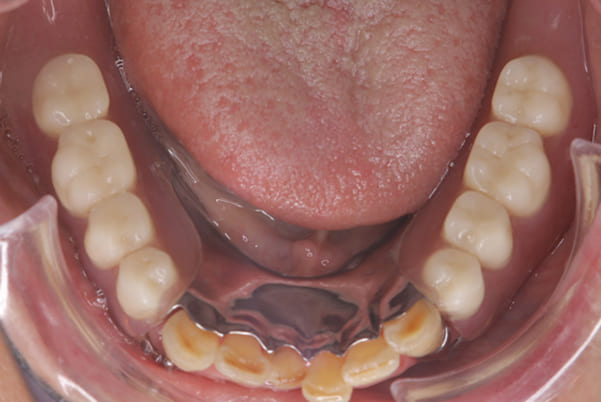

下顎治療後

治療用入れ歯は患者様とご相談し、早急にお痛みをとり、お食事ができることをご希望されていたため、歯を抜くと同時に仮の入れ歯が入りお食事をされた後のお写真です。直ちに、お痛みを取り除き、お食事ができるような治療計画としました。

精密義歯は、歯をぬいたあと歯肉が治ってから、精密な入れ歯を作製しました。治療中も、仮の入れ歯があるため、普段の生活に支障がなく、また仮の入れ歯を実際使ってのご意見、ご希望(バネが気になる)をお聞きした上で、精密な義歯に、ご希望を反映し作製しました。

従来の方法では、歯を抜いてから入れ歯を作るまでは、歯茎の治りを待つため数か月かかりますが、患者様のご希望で、見た目、食べることに支障が出ないよう、抜歯と同時に入れ歯を装着し、歯がない期間がない入れ歯を作製したため、その日から、お食事や外出が可能となりました。

また、当然ではありますが、患者様も残りの歯をこれ以上失いたくないとのご希望が強く可能な限り、残りの歯に負担がかからない機能性を重視し、また、バネがなるべく見えない設計とし、機能と審美の両方に重きをおいた入れ歯を作製し、お痛みなく、お食事も召し上がられるようになりました。